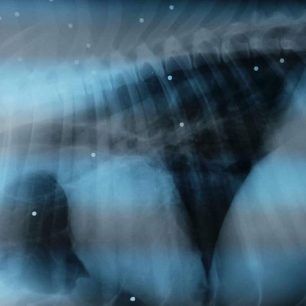

Λακωνία: Σκελετωμένο και εξαντλημένο σκυλί στο χωριό Καλονιοί της Ανατολικής Μάνης

Στο χωριό Καλονιοί της Ανατολικής Μάνης περιφέρεται στην κυριολεξία σκελετωμένο το σκυλί Κούρτσχααρ που εντόπισε εκεί πριν από μερικές εβδομάδες ένας επισκέπτης της περιοχής. Σύμφωνα με πληροφορίες του www.zoosos.gr το ζώο που έχει και ακρωτηριασμένη ουρά – αν και αυτές οι επεμβάσεις και στα κυνηγόσκυλα απαγορεύονται στην Ελλάδα εδώ και 23 χρόνια – δεν είναι αδέσποτο, αλλά ο ιδιοκτήτης του το έχει εξαθλιώσει με την αδιαφορία του.